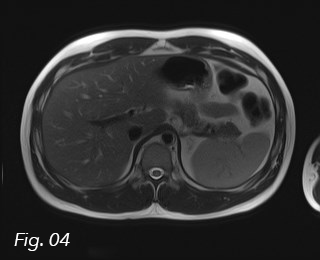

Fig. 5: Axial T1 in-phase image. The area with fatty infiltration is isointense to the surrounding liver parenchyma (arrow).